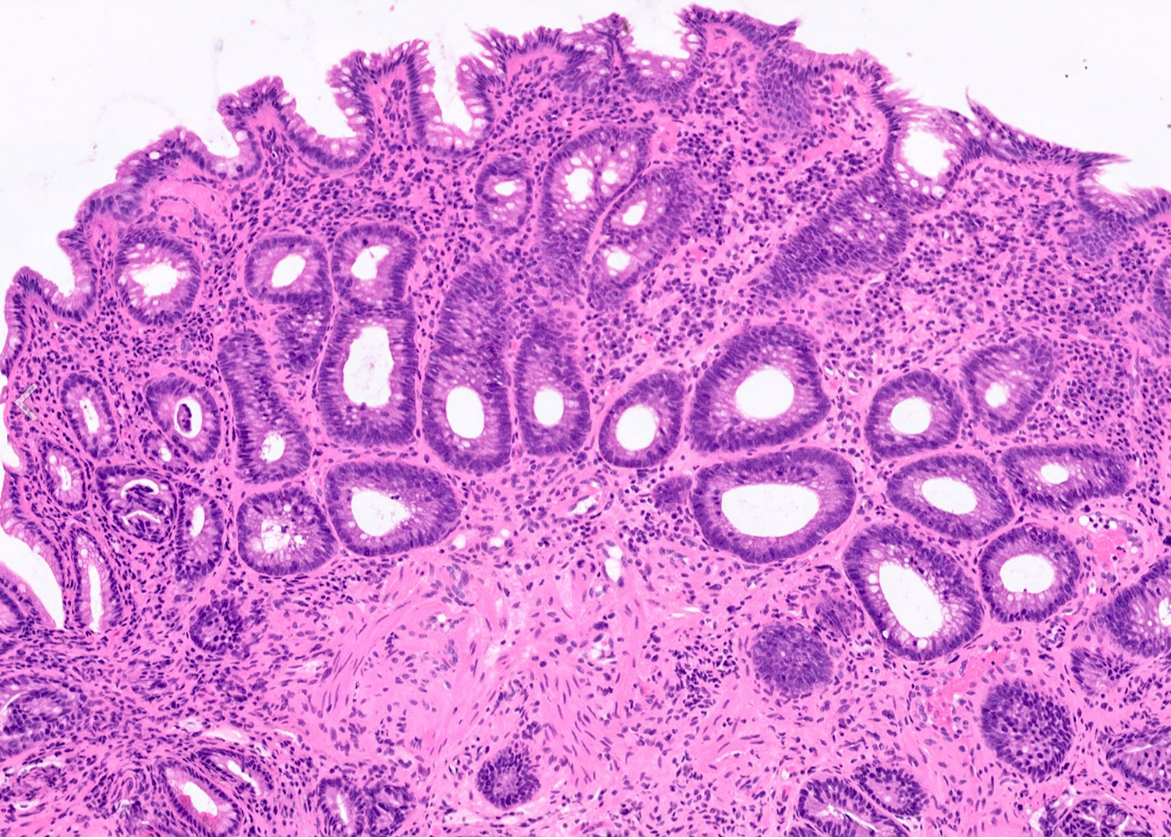

25M rectosigmoid polyp

Dx

Key features

Juvenile polyp

Key features:

Characterized by an abundance of edematous lamina propria with inflammatory cells and cystically dilated glands lined by cuboidal to columnar epithelium with reactive changes (gastric type epithelium??)

Dilated glands filled with mucus and inspissated inflammatory debris